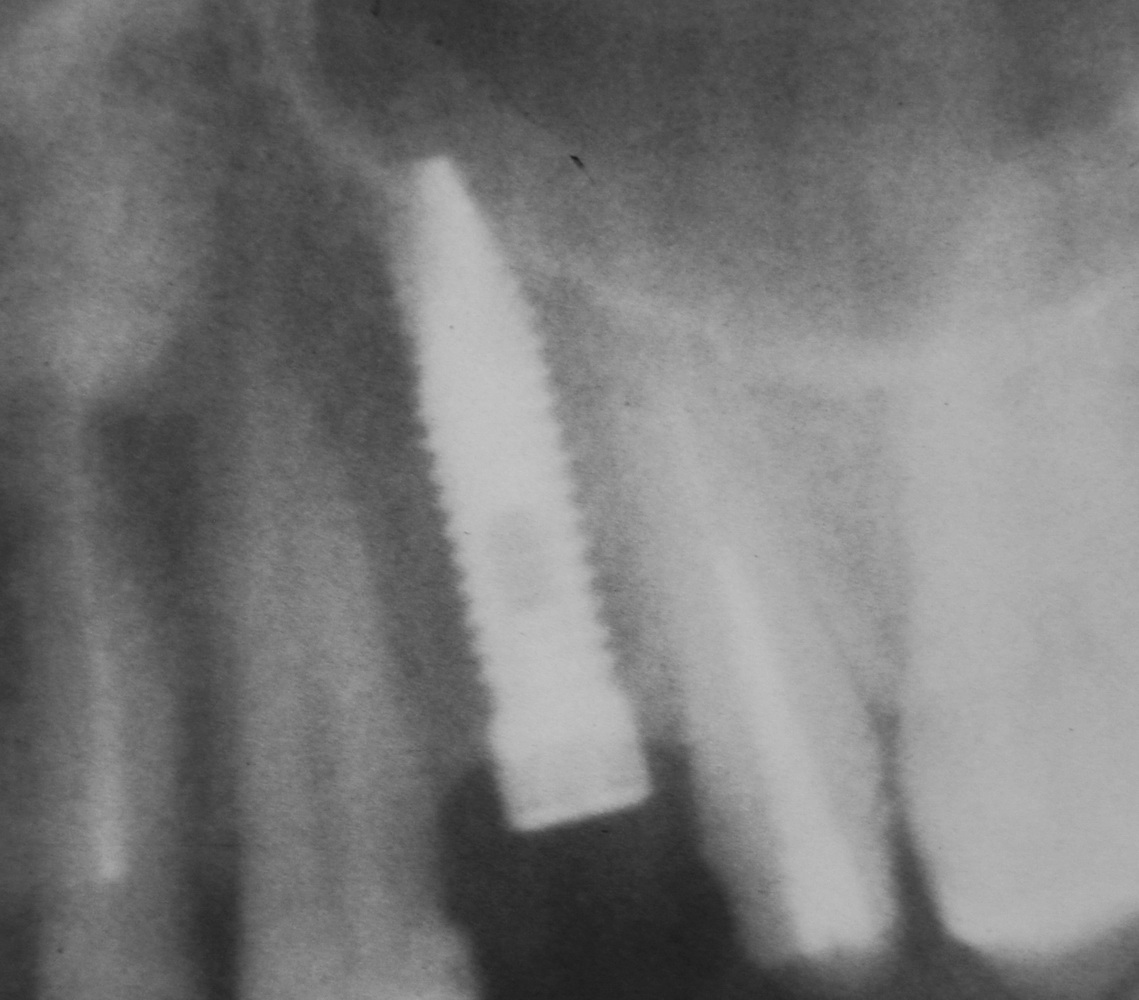

Оптимальное расстояние от дна гайморовой пазухи до верхней точки альвеолярного гребня верхней челюсти, при котором возможна стабилизация импланта длиной 10-11 мм – не менее 3-4 мм. Однако, в некоторых случаях имплантат длиной 11 мм удается стабилизировать в меньшем объеме костной ткани (рис 46, 47, 48):

Рисунок 46, 47, 48. Стабилизация импланта при толщине костной ткани менее 3 мм: слева – установка импланта после синуслифтинга, в центре – заполнение субантрального пространства спейсером, справа – рентгенологический контроль.